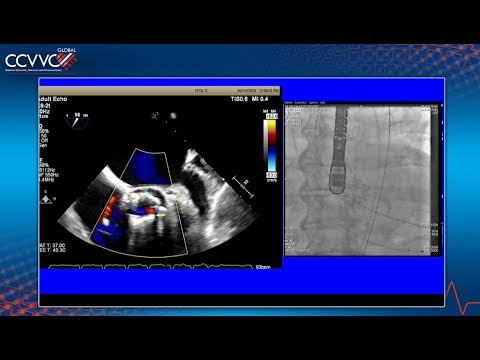

Live Case 12 - CoreValve TAVR for Bioprosthetic Stenosis - CCVVC 2017